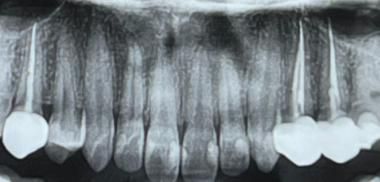

잇몸에 염증이 있는 것은 아닌지 궁금합니다 ㅠㅠ 우측 2개 신경치료한 부분은 손으로 흔들면 살짝 욱신거리고 씹을 땐 문제 없습니다. 좌측은 그냥 멀쩡해요. 신경치료 4개월차입니다. 사진을 확대하셔야 신경치료 치아 3개가 보이실 것 같습니다 ㅠㅠ

사진으로 봤을 경우에는 크게 문제가 없는것으로 보입니다. 하지만 사진의 화질이 좋지 않고 왼쪽의 뒤의 치아는 뿌리부분이 어두워 보이기 때문에 좀더 정확한 확인이 필요해 보입니다.

엑스레이 상으로 신경치료도 잘되어잇고 문제가 잇어 보이진 않습니다. 관리만 잘하시면될것같습니다.

세개 다 엑스레이상 큰 문제는 보이지 않습니다 다만 엑스레이에 보닐정도면 진행이 꽤 된 염증상태입니다 엑스레이에서 보이지 않을 정도의 치아 염증일 수도 있습니다